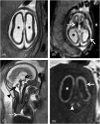

Human cytomegalovirus (CMV) is an ubiquitous pathogen, with a high worldwide seroprevalence. When acquired in the prenatal period, congenital CMV (cCMV) is a major cause of neurodevelopmental sequelae and hearing loss. cCMV remains an underdiagnosed condition, with no systematic screening implemented in pregnancy or in the postnatal period. Therefore, imaging takes a prominent role in prenatal diagnosis of cCMV. With the prospect of new viable therapies, accurate and timely diagnosis becomes paramount, as well as identification of fetuses at risk for neurodevelopmental sequelae. Fetal magnetic resonance imaging (MRI) provides a complementary method to ultrasound (US) in fetal brain and body imaging. Anterior temporal lobe lesions are the most specific finding, and MRI is superior to US in their detection. Other findings such as ventriculomegaly, cortical malformations and calcifications, as well as hepatosplenomegaly, liver signal changes and abnormal effusions are unspecific. However, when seen in combination these should raise the suspicion of fetal infection, highlighting the need for a full fetal assessment. Still, some fetuses deemed normal on prenatal imaging are symptomatic at birth or develop delayed cCMV-associated symptoms, leaving room for improvement of diagnostic tools. Advanced MR sequences may help in this field and in determining prognosis, but further studies are needed.